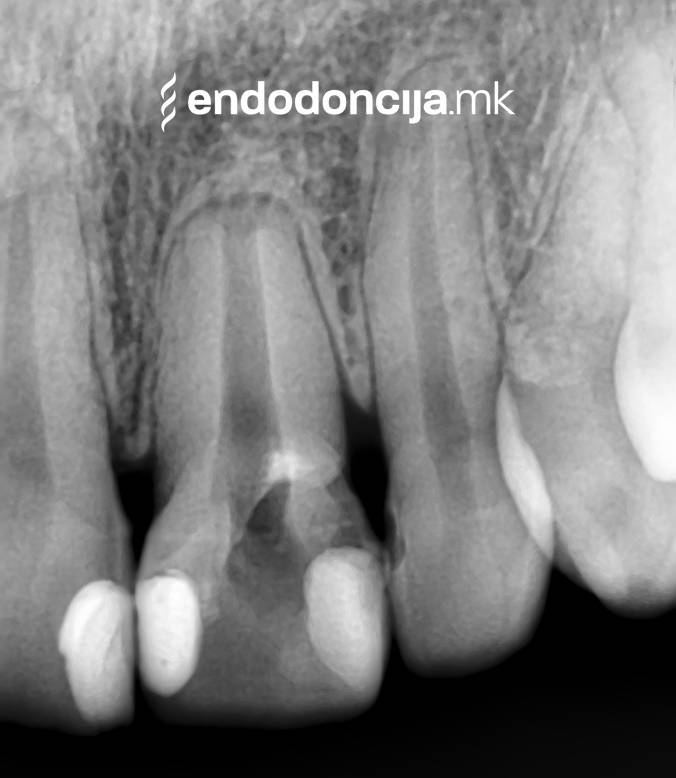

Κατά τη διάρκεια της επεξεργασίας του ριζικού σωλήνα, τα λεπτά όργανα ενδέχεται να σπάσουν. Αυτό μπορεί να αποτελέσει εμπόδιο για την πλήρη προετοιμασία και τον καθαρισμό του ριζικού σωλήνα. Με μια μικροσκοπική επεξεργασία του ριζικού σωλήνα μπορεί να είναι δυνατή η απομάκρυνσή τους υπό ορισμένες συνθήκες, χωρίς να καταστρέφεται η ουσία των δοντιών.